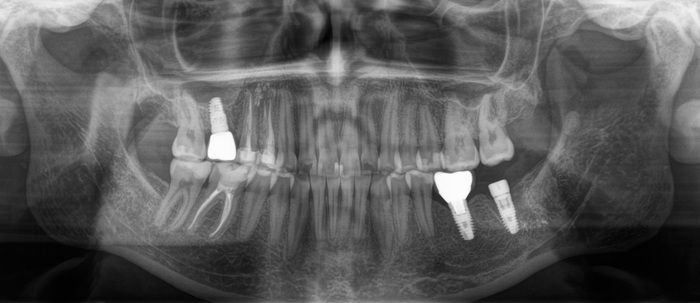

И вот эти проблемы дали о себе знать. Июнь 2023 года, спустя каких-то 5 лет после установки коронки на 7й нижний имплантат винт ломается и в нем.

Прикус:

За эти годы ситуация усугубилась, стираемость зубов прогрессировала.

Вот как выглядели зубы в 2018 году:

А это через каких-то 3 года, 2021:

Обратите внимание, как сильно стерлась верхняя «двойка» и нижний клык:

Ниже ситуация от июня 2023:

Есть такое понятие, как клыковое ведение (или клыковая дезокклюзия) – это разобщение задних зубов во время боковых движений нижней челюсти. Иными словами, (прочтите медленно) при смещении нижней челюсти в сторону, двигаясь клыком нижней челюсти по клыку верхней челюсти на момент контакта бугров, у боковых зубов не должно быть контакта. В данном случае он есть именно на 7ках:

Оранжевым цветом отмечена стираемость зубов, а красным место контакта.

Зубы стерлись, высота прикуса занизилась. В связи с чем появился преждевременный контакт керамической коронки на нижнем 7м зубе (керамика не стирается) и верхним 7м зубом.

(Вы можете отметить, что на 6ке тоже керамическая коронка. Не стоит забывать, что ее переделывали. Следовательно, она была подогнана под истертые зубы).

Поэтому, из-за постоянной перегрузки винт и сломался. Могучий Иван снова достал винт, заменил его на новый и прикрутил обратно ту же самую коронку. Подточил 7й зуб, вывив его из преждевременного контакта с нижним. (снимки сделаны при помощи зеркала) на 3,4,5,6 зубах отпечатана копирка, на 7м нет: